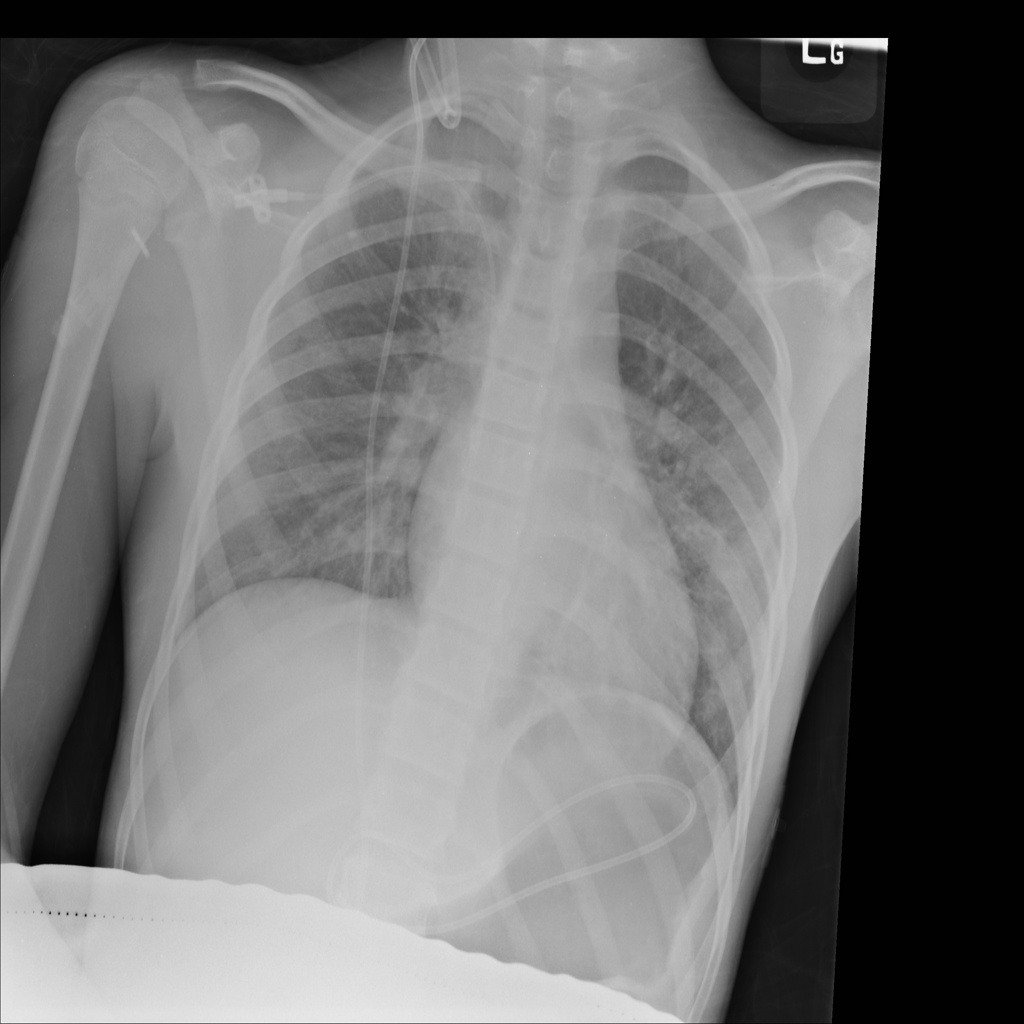

PAT-6B69 · IMG-027Consolidation

PAT-6B69 · IMG-027

AP